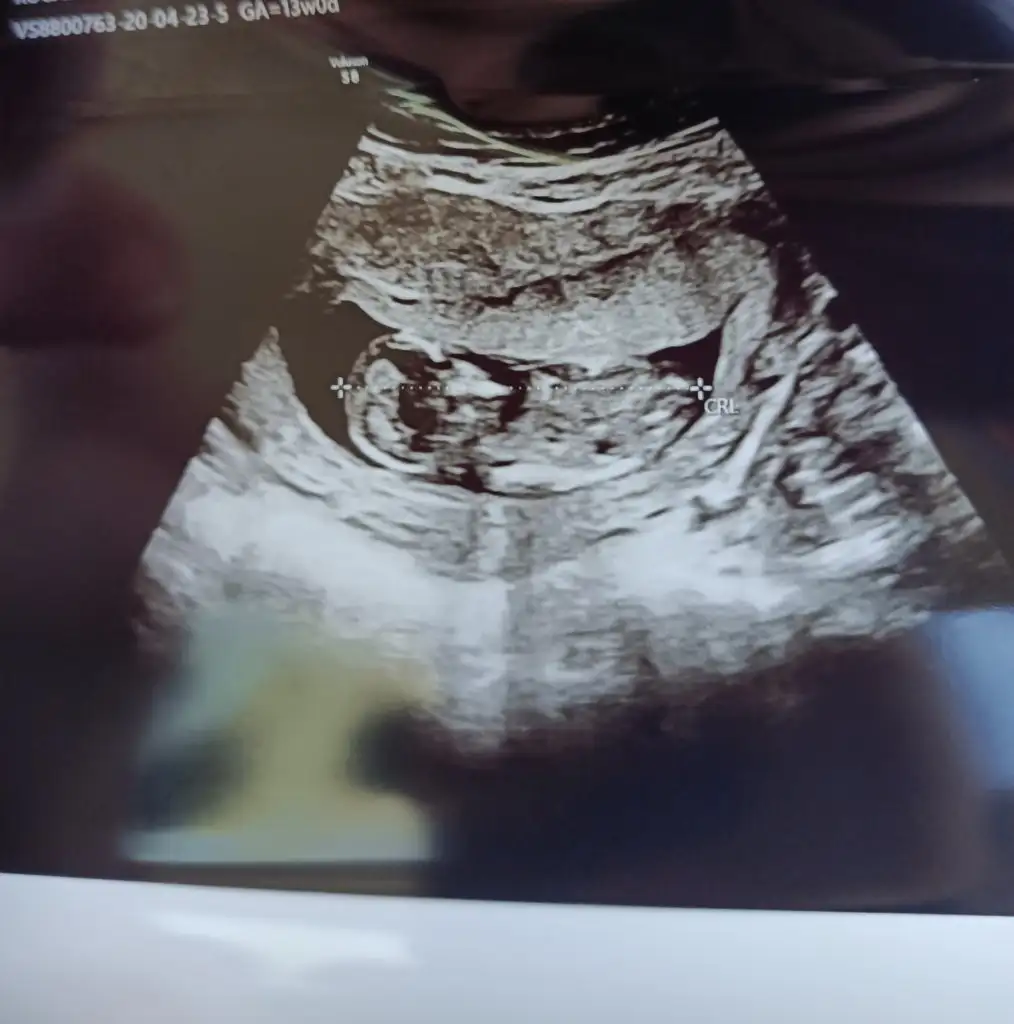

Merhabalar anlayanlar benim görüntülerede bakabilirmi 13 haftalık olduk merak ediyorum 😉

Eklentiler

• IMG20200423112010.webp

IMG20200423112010.webp

25,9 KB · Görüntüleme: 54

• IMG20200422153547.webp

IMG20200422153547.webp

25,6 KB · Görüntüleme: 54